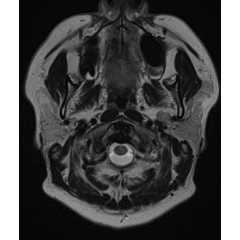

※ 記事半ばに脳のMRI写真が出てきます。苦手な方はご注意ください

顔面神経麻痺は「顔がまがってきた」、「眼が閉じにくい」、「水が口からこぼれる」、「口の動きが悪くなる」など、顔の筋肉が動きづらくなる病気です。